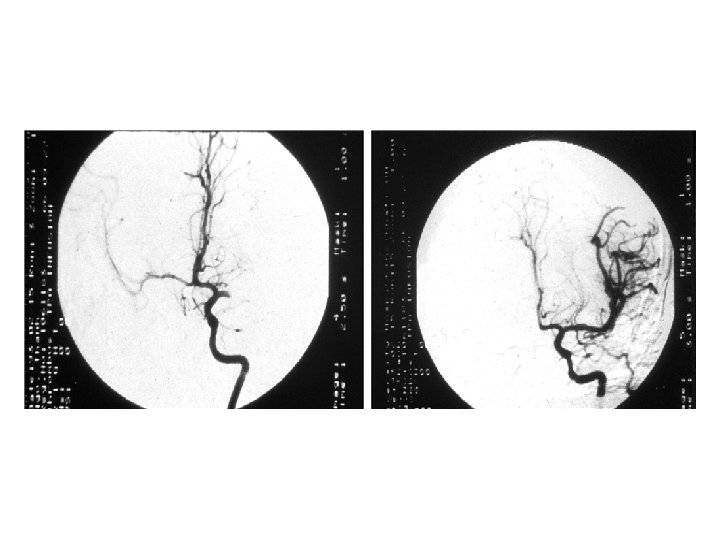

INTRA-ARTERIAL ADMINISTRATION OF THROMBOLYTIC AGENTS • Potential advantages v. Higher concentration of medication at site v. Lower systemic doses might improve safety • Potential disadvantages v. Facilities not widely available v. Time required to mobilize resources • No head-to-head comparisons with IV therapy

INTRA-ARTERIAL PROUROKINASE PROACT - II STUDY Randomized, clinical trial - 54 centers 121 Patients - pro. UK and heparin 59 Patients - heparin Outcomes measured at 90 days Blinded to treatment allocation Slight or no disability Furlan et al, JAMA 1999; 282: 2003 -2011

RECANALIZATION AND INTRACRANIAL BLEEDING PROACT-II STUDY Recanalization Pro. UK (%) Heparin (%) 1 Hour 4% -- 2 Hours 19% 2% Symptomatic hemorrhage 10% 2% CT hemorrhage - 1 day 35% 13% Furlan et al, JAMA 1999; 282: 2003 -2011

• To date, no head-to-head comparisons of intravenous versus intra-arterial therapy v. Intravenous (rt-PA) < 3 hours v. Intra-arterial (Pro UK) < 6 hours • No evidence that intra-arterial therapy is either more effective or safer